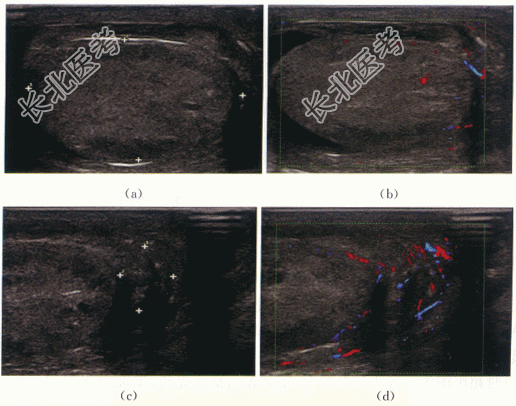

二、影像资料及诊断

1.影像资料

2.诊断

右侧睾丸附睾缺血性坏死伴急性化脓性炎。